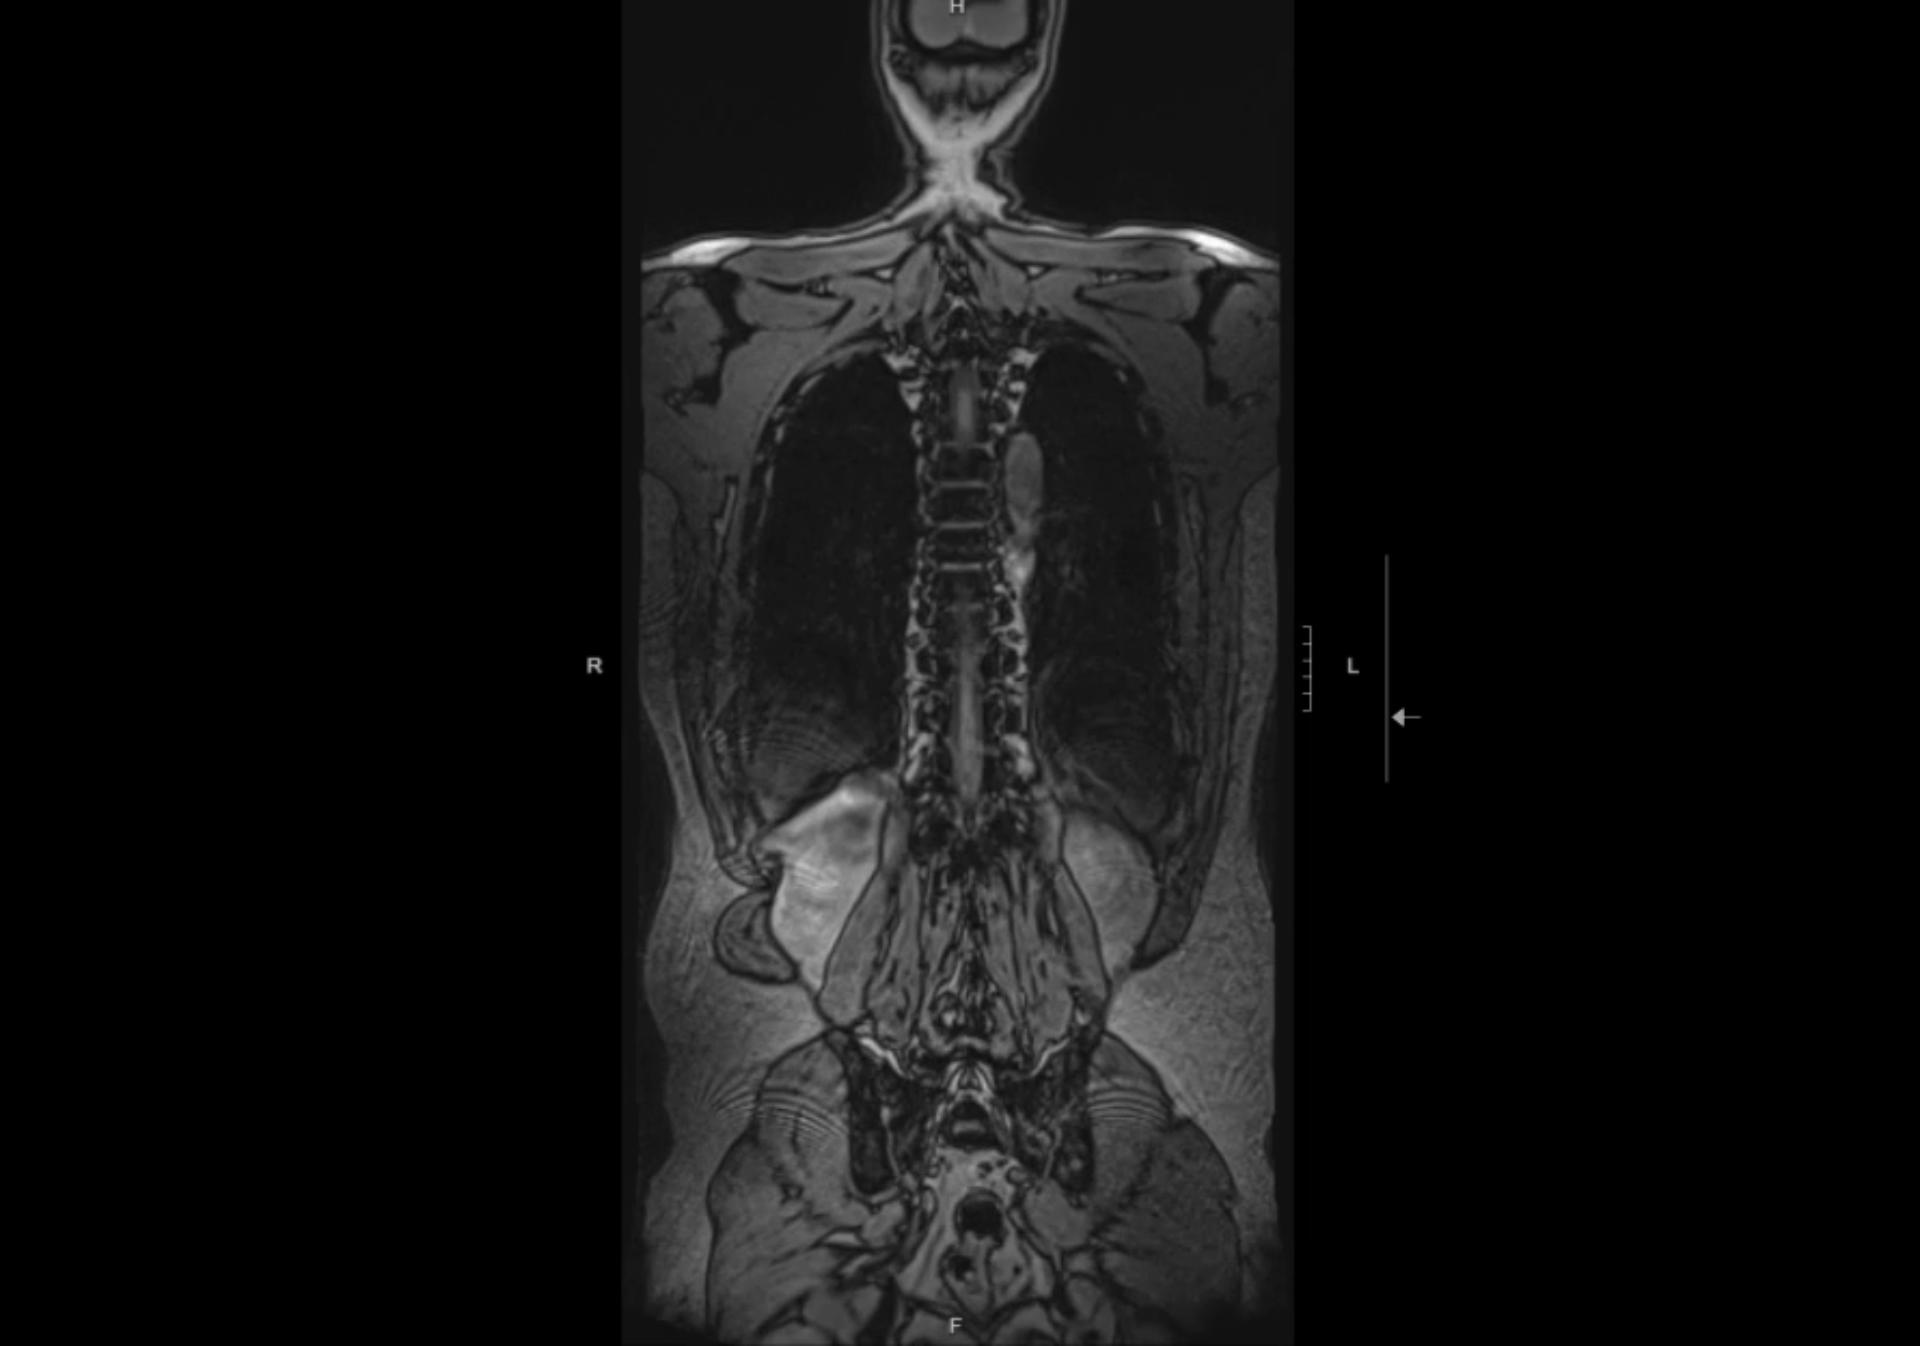

Oh! A lot has happened since the last post. I saw a doctor, got an injection in my hip (that did not work and offered no relief) and then I got an increase in my medication, and then I got an MRI and then another increase in my medication (sigh) and sometimes I have to take out-of-state medication.

So what’s next? Well, I got an EMG (electromyography) and the good news is my nerves are not damaged. So I saw another doctor this week and we’re going to move forward with getting me two injections into each side of my spine because they can’t do just one from the back due to the spacing. (Eww.)